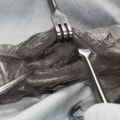

脊髄の減圧、脊柱管の再構築・安定化を目的に、片側椎弓切除術およびMatrixMANDIBLE Plateによる椎体固定を実施しました。

隣接椎体を架橋するようにプレートを設置しました。

他院にて左大腿骨遠位の成長板骨折(salter-harrisⅠ型)が認められており、治療相談を目的として来院。当院にて、キルシュナーワイヤーを用いたピンニングにより骨折部位の整復を行いました。術後の経過は良好で、現在も経過観察中です。

Arthrex社のターゲティングデバイスを用いてピンニングの位置を調整することで、確実な固定を行っています。当院ではこの手術器具以外にも、人の手術にも使用される様々な器具を導入し、手術精度を高め、また医療メーカーと新しい器具の開発、試作にも取り組んでおります。